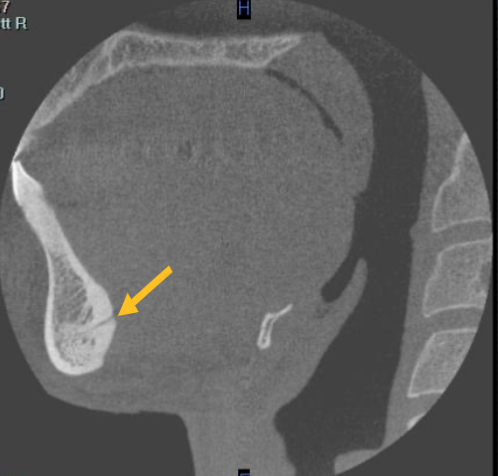

mental foramen

what is the structure indicated by the arrow